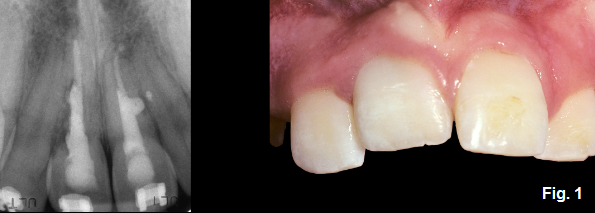

In this example, we have an 11-year-old male who received trauma to the maxillary anterior when he was 10 years old and subsequently had ankylosis of tooth #8. (Fig. 1)

As can be seen radiographically, the root resorption is occurring at a significant rate given that the trauma only occurred approximately one year ago. At this time though, there hasn’t been much change in the incisal edge or FGM positions. With this in mind, the tooth can be monitored. The parents are informed that continued recalls are imperative so that the tooth can be extracted prior to formation of a significant hard and soft tissue defect. This must be stressed to the parents because if the patient gets lost in the system or doesn’t return for recalls the defect will become greatly amplified and the treatment needed to correct it will be more difficult. At the age of 12, a change in the incisal edge position and FGM location can be seen. (Fig. 2)